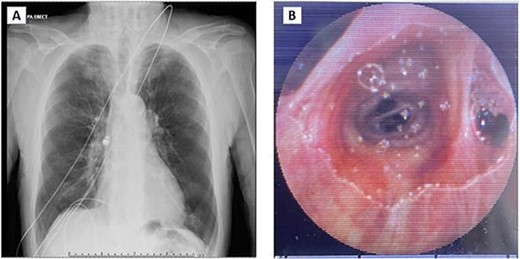

An 87-year-old gentleman was investigated for anaemia, and a positive faecal blood test was booked for capsule endoscopy. This was done as an outpatient procedure using a Pillcam SB 3 system (Medtronic, MN, USA). After necessary directions, the patient was asked to swallow the capsule. Following swallowing of the capsule, the patient started to cough intermittently and desaturated requiring supplemental oxygen. On the monitor, the capsule was not moving and did not appear to be in the oesophagus. Chest X-ray confirmed the pill was in the right main bronchus (Fig. 1A). The patient was then referred to the Thoracic Surgical service for urgent evaluation and management.

(A) Chest X-ray showing capsule in the right main bronchus. (B) Capsule lodged in bronchus intermedius showing endobronchial anatomy.

Post review, the patient consented to rigid/flexible bronchoscopy and retrieval of a foreign body. Because of the prevalent coronavirus disease 2019 (COVID-19) pandemic, the procedure was performed with full COVID precautions. A flexible bronchoscope evaluation was performed with the patient under general anaesthesia and through a size 8.5 endotracheal tube (ETT). The capsule was found to be lodged in the bronchus intermedius (Fig. 1B). The size of the capsule (26.2 × 11.4 mm) and its very smooth surface meant that it could not be grasped by available endobronchial instruments. Attempts to trap it in a Nitnol tipless stone extractor basket (2.2 cm) were not successful. We subsequently tried using Fogarty catheters (of sizes 3–7). Although we were able to dislodge the capsule into the trachea, the size discrepancy between the balloon and trachea and perhaps because of the weight of the capsule, it could not be delivered into the upper trachea it repeatedly slipped back to the bronchus on the right. Because of this repeated slippage, the patient was placed in a stip Trendelenburg position. The use of gravity prevented slippage of the capsule distally. After this manoeuvre, the capsule was drawn to the tip of the ETT. The capsule was wedged between the balloon of the Fogarty and the ETT tip and they were all withdrawn as a unit (Fig. 2). The capsule was brought outside the vocal cords and retrieved using Magill forceps. The patient was subsequently reintubated until subsequent extubation. The postoperative recovery was uneventful.